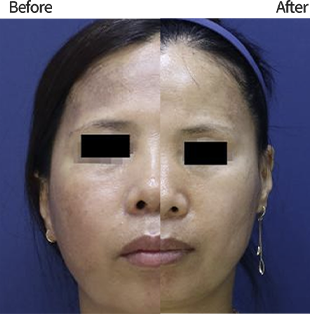

ลดความหย่อนคล้อย

ลดความหย่อนคล้อย